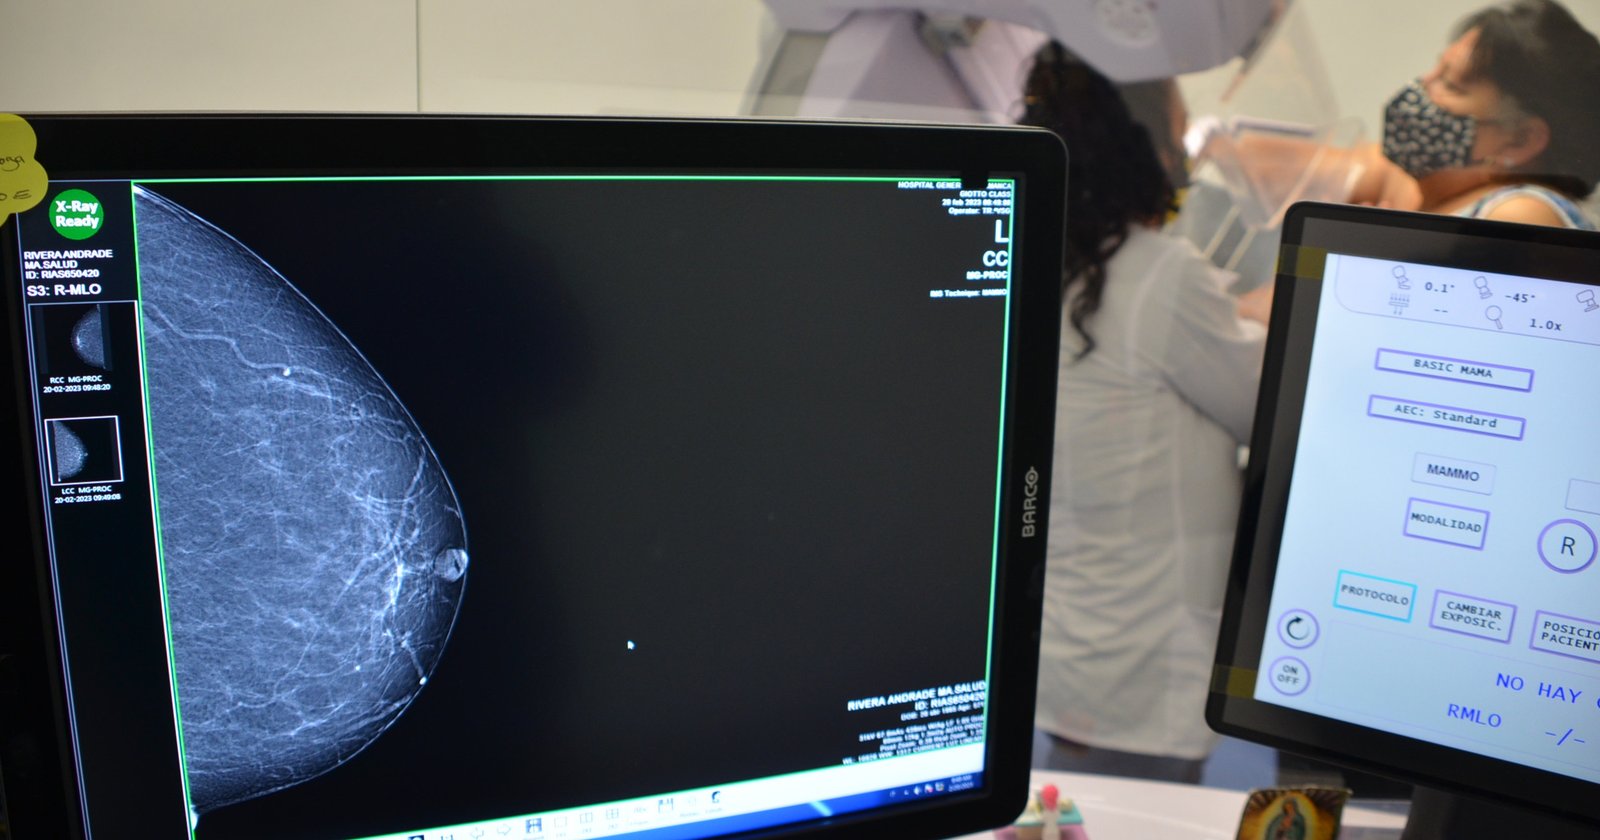

Martínez exhortó a promover la detección temprana del cáncer de mama, con la autoexploración de mamas a partir de los 20 años, el examen clínico a partir de los 25 años, y la mastografía en mujeres de 40 y hasta 69 de edad.

Además, el Sistema de Salud Gto cuenta con 17 mastógrafos distribuidos estratégicamente por todo el Estado, mediante los cuales se refuerza este diagnóstico.